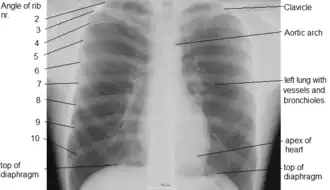

Landmarks

In the average person, the diaphragm should be intersected by the 5th to 7th anterior ribs at the mid-clavicular line, and 9 to 10 posterior ribs should be viewable on a normal PA inspiratory film. An increase in the number of viewable ribs implies hyperinflation, as can occur, for example, with obstructive lung disease or foreign body aspiration. A decrease implies hypoventilation, as can occur with restrictive lung disease, pleural effusions or atelectasis. Underexpansion can also cause interstitial markings due to parenchymal crowding, which can mimic the appearance of interstitial lung disease. Enlargement of the right descending pulmonary artery can indirectly reflect changes of pulmonary hypertension, with a size greater than 16 mm abnormal in men and 15 mm in women.[6]

Appropriate penetration of the film can be assessed by faint visualization of the thoracic spines and lung markings behind the heart. The right diaphragm is usually higher than the left, with the liver being situated beneath it in the abdomen. The minor fissure can sometimes be seen on the right as a thin horizontal line at the level of the fifth or sixth rib. Splaying of the carina can also suggest a tumor or process in the middle mediastinum or enlargement of the left atrium, with a normal angle of approximately 60 degrees. The right paratracheal stripe is also important to assess, as it can reflect a process in the posterior mediastinum, in particular the spine or paraspinal soft tissues; normally it should measure 3 mm or less. The left paratracheal stripe is more variable and only seen in 25% of normal patients on posteroanterior views.[7]